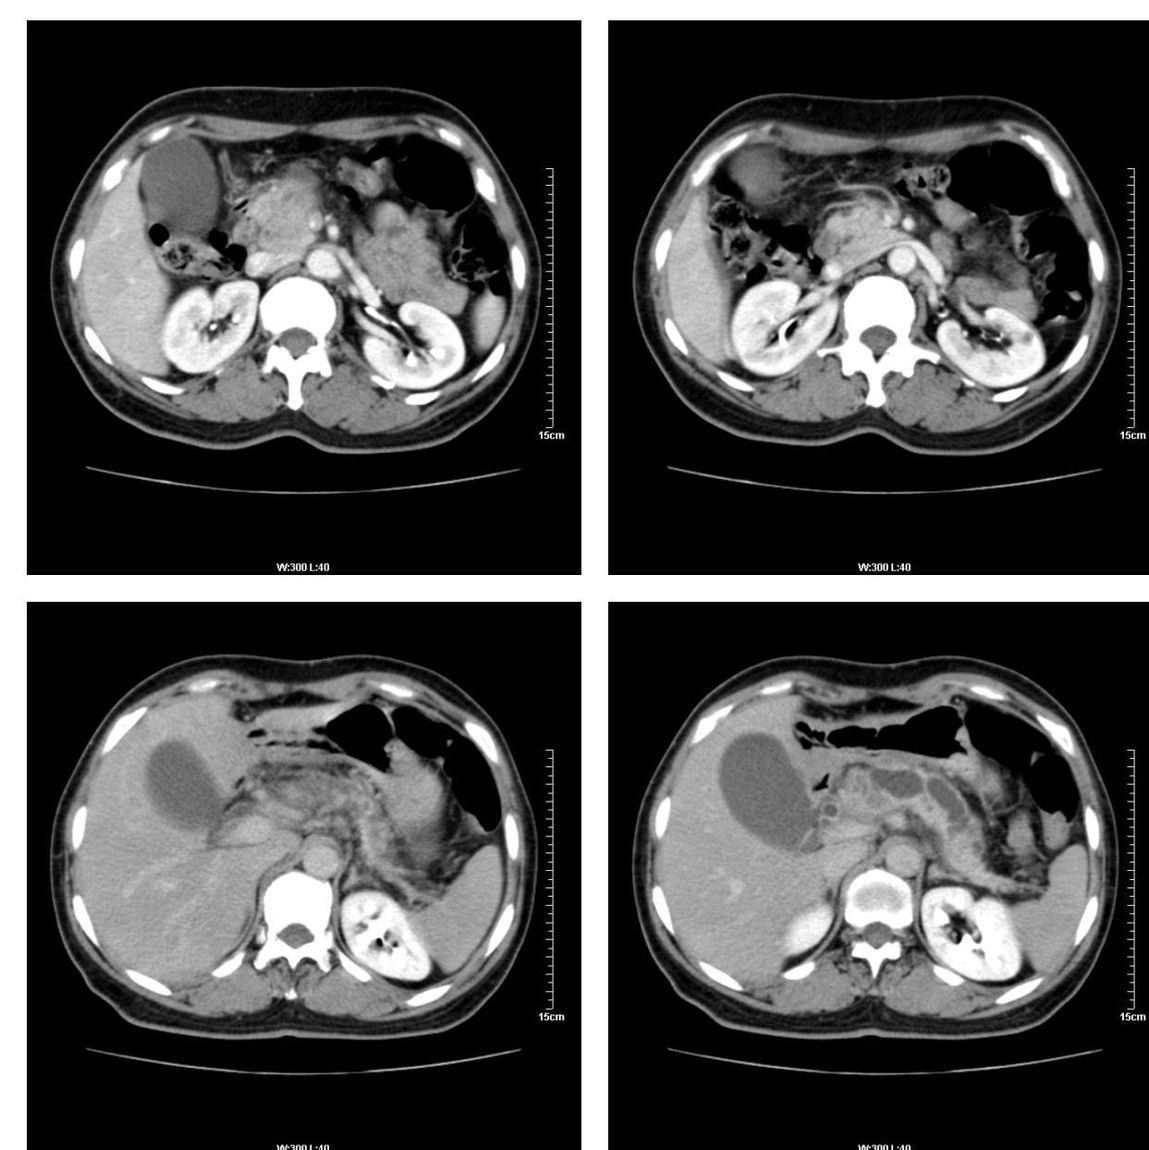

标题: CT13800:女性,52岁。腹痛、腹胀、消瘦及乏力5个月。 [打印本页]

标题: CT13800:女性,52岁。腹痛、腹胀、消瘦及乏力5个月。

慢性胰腺炎、胰腺假囊肿形成,胆总管梗阻,胆囊扩张

胰腺癌可能大

考虑胰头癌

考虑胰腺囊腺癌。

考虑胰头癌可能。

各期时间抓的不太好,门静脉始终显示不佳(门脉瘤栓形成?)。